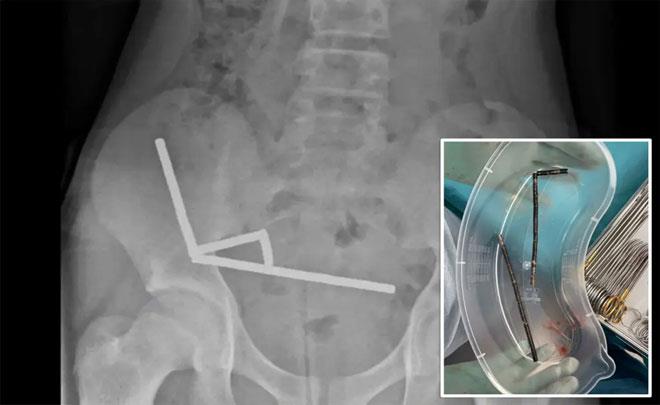

لەڕێی وێنەی تیشکەوە دەرکەوتووە موگناتیسەکان لەناو گەدەی گەنجەکەدا یەکیان گرتووە و چوار هێڵی ڕێکیان دروستکردووە، هێزی موگناتیسەکە بۆتە هۆی شیبونەوەی بەشێک لە شانەی ڕیخۆڵە ئەستورە و باریکەی، پاش نەشتەرگەری و 8 ڕۆژ مانەوە لە نەخۆشخانە نەخۆشەکە گەڕاوەتەوە ماڵەوە.